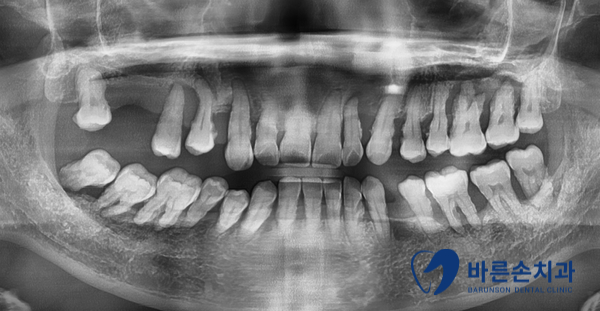

그럼 엑스레이로 상태를 확인해 볼까요?!

1)정상잇몸 사진은 치석이 보이지 않고 치조골(잇몸뼈)이 수평으로 일정하게 이어진 것을 볼 수 있습니다.

2)치주질환 잇몸 사진은 치석이 보이고 치조골 높이가 낮아지면서 잇몸뼈가 수직으로 흡수된 것이 보입니다.

잇몸뼈가 많이 녹을 수록 치아가 많이 흔들리게 되고 이런걸 바로 ‘풍치’ 라고 합니다.

치아가 충치도 없고 건강해도 치아를 잡아주는 잇몸뼈가 약해지면 치아를 뺄 수 밖에 없어집니다.

사진 속 환자분도 결국 발치를 했답니다…너무 안타깝죠ㅠㅠ

치주질환 엑스레이